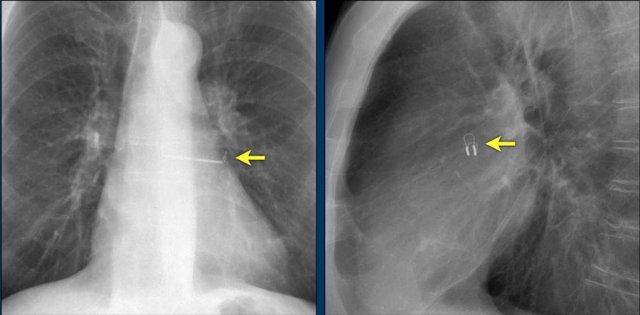

MitraClip

Ở những bệnh nhân hở van hai lá nặng và không phải là ứng viên cho phẫu thuật tim hở, sửa chữa van hai lá qua đường ống thông, được gọi là MitraClip, là một phương pháp điều trị phù hợp.

Trung tâm của các lá van hai lá được khép lại bằng MitraClip nhằm giảm thiểu tình trạng hở van, đồng thời vẫn để lại đủ khoảng trống cho dòng máu đi từ tâm nhĩ trái sang tâm thất trái (hình minh họa).